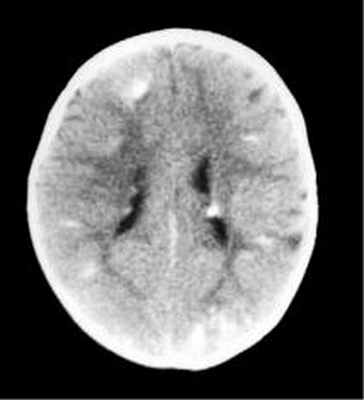

Субэпендимарные кальцификаты и корковые туберсы на КТ головного мозга ребенка с туберозным склерозом

Наиболее типичными нарушениями в головном мозге являются корковые туберсы и субэпендимарные узлы. Туберсы могут быть как единичными, так и множественными, располагаются в виде выступов над единичной или прилегающими бороздами коры, расширяя их. Субэпендимарные узлы локализуются в стенках боковых желудочков и, реже, в стенках III и IV желудочков мозга. У новорожденных субэпендимарные узлы редко бывают кальцифицированными. По мере роста ребенка наблюдается постепенное отложение кальция в субэпендимарных узлах.

Субэпендимарные узлы в 10% случаев трансформируются в гиганто-клеточную астроцитому, которые манифестируют обычно между 5 и 10 годами жизни, имеют тенденцию к росту и локализуются у отверстия Монро